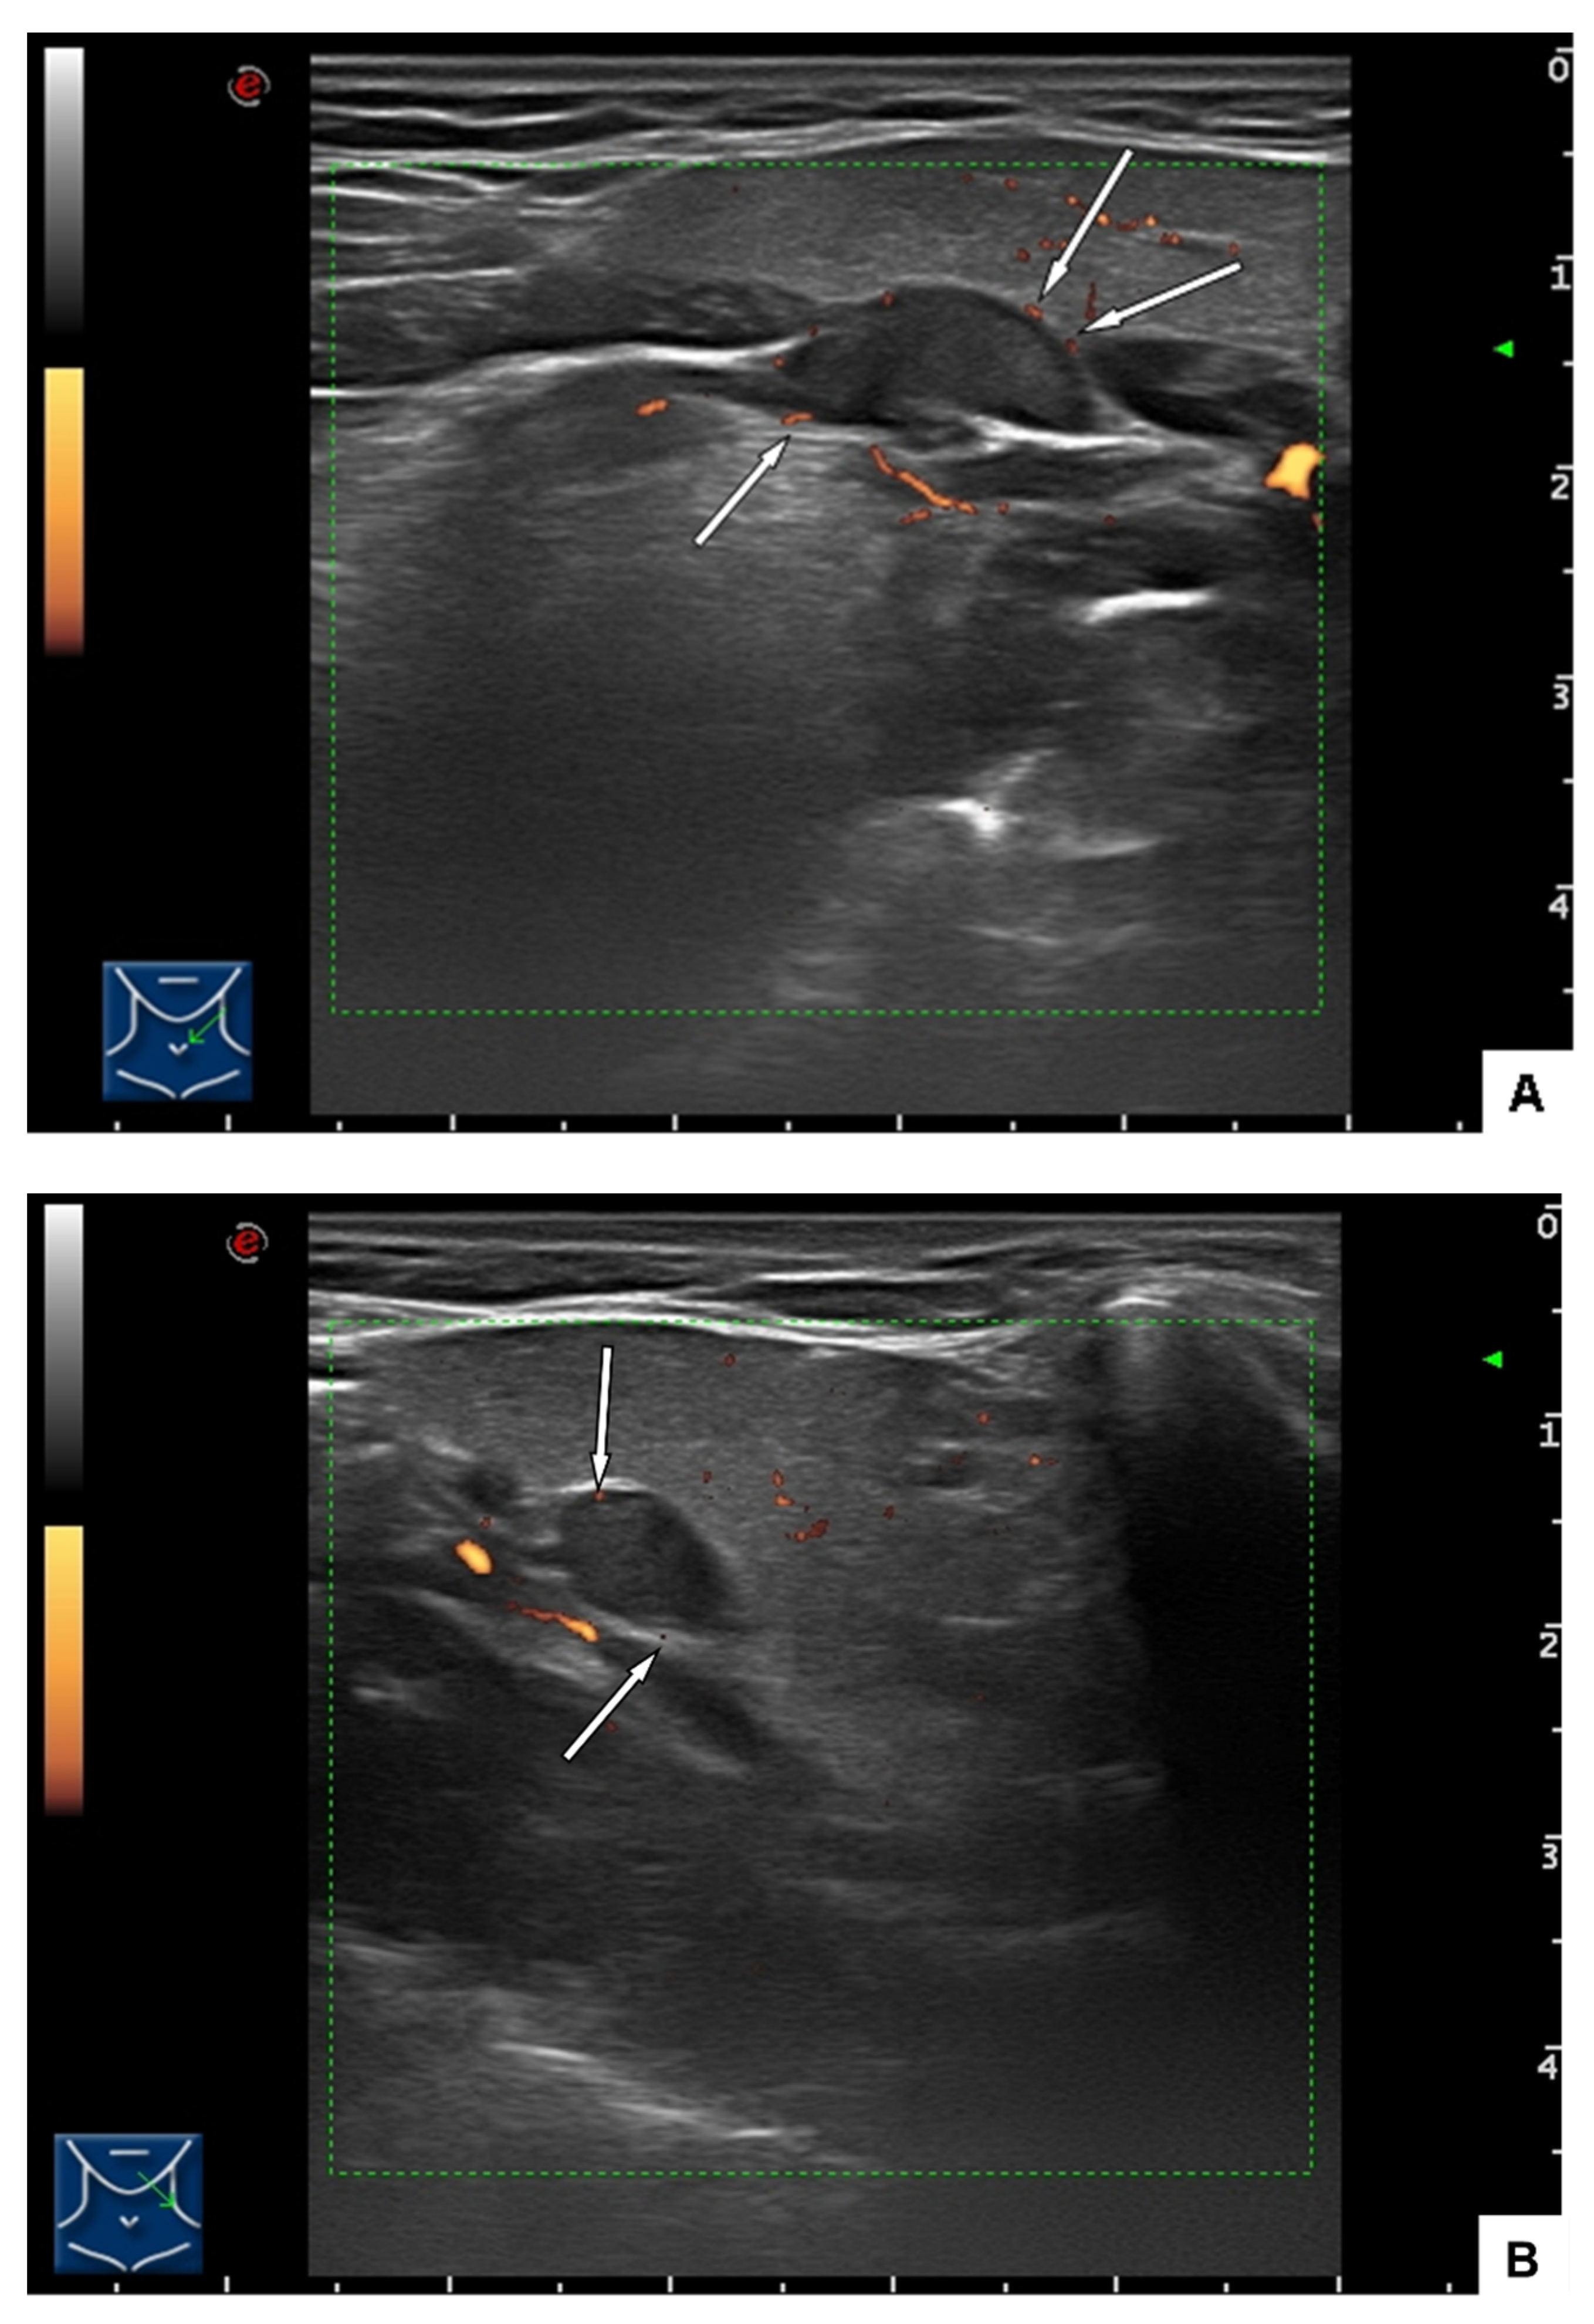

2.1. Clinical Findings and Imaging